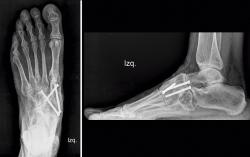

En el estudio mediante radiología simple en carga (Figura 2) se aprecia en la proyección dorsoplantar una desestructuración en la primera cuña con fragmentación y desplazamiento medial del fragmento proximal, así como cambios degenerativos escafocuneanos e intercuneanos. En la proyección lateral vemos un hundimiento de la columna medial a nivel transcuneano. En ambas proyecciones se aprecia una buena consolidación en el pie contralateral (clínicamente asintomático).

Figura 2. Radiografía preoperatoria.